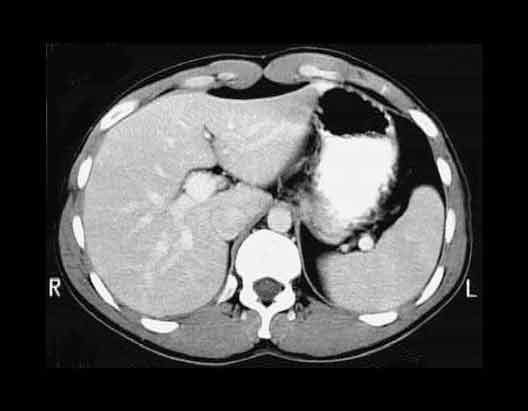

Abdominal CT at T11

1. Liver

2. Azygos vein

3. Gas bubble in stomach

4. Stomach

5. Spleen

6. Abdominal aorta